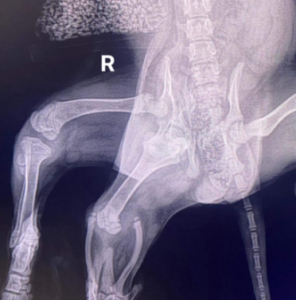

Uma filhote nascida com seis patas foi encontrada abandonada no estacionamento de um supermercado.

A spaniel fêmea de 11 semanas de idade foi descoberta abandonada do lado de fora da filial do B&M em Pembroke Dock, Pembrokeshire, na semana passada.

Além de suas patas traseiras extras, também foi revelado que ela possui duas vulvas.

Mais de £2.000 foram arrecadados para a remoção cirúrgica de suas duas patas traseiras adicionais, mas os veterinários alertaram que ela também poderia perder uma de suas patas traseiras “normais” restantes no processo.

Após ser resgatada em estado de angústia por um transeunte na quarta-feira, o animal foi levado para o Greenacres Rescue, perto de Haverfordwest, Pembrokeshire, pelo responsável pelo canil do município. Ela passou por uma avaliação na clínica veterinária Fenton, na cidade, onde recebeu o nome de Ariel, em referência à personagem da Disney, A Pequena Sereia – a equipe a comparou às patas traseiras adicionais da filhote, parcialmente fundidas, a uma cauda de sereia.